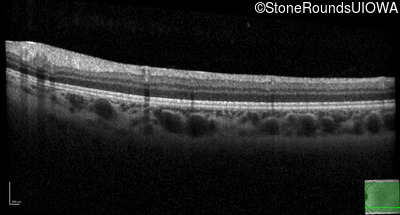

Optical Coherence Tomography - Right - 20/25

Exemplar / OCT Stack